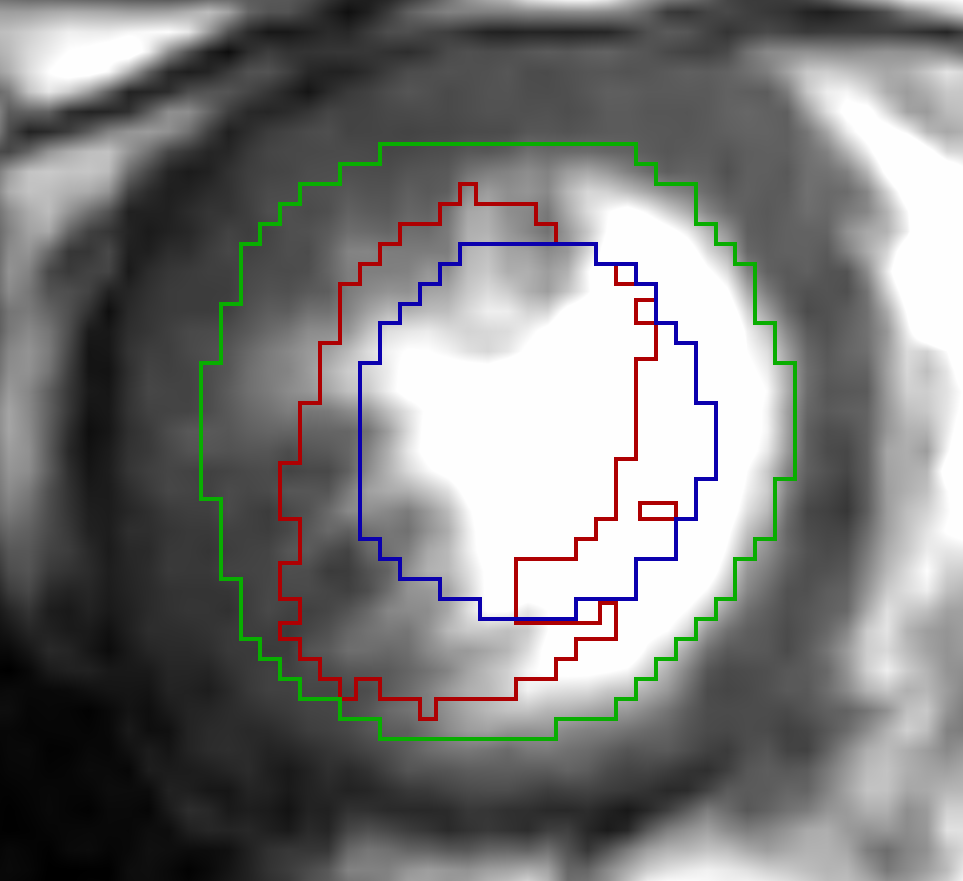

For the cardiac datasets the DVF for mapping the systolic phase to diastolic phase showed better results (DSC: 0.90, HD: 10.35 mm, ASSD: 1.49 mm) compared to the registration from diastolic to systolic phase (DSC: 0.81, HD: 13.12 mm, ASSD: 1.95 mm). We attribute this direction-dependent behaviour to the resampling of the Sunnybrook datasets. In the diastolic images the border of the LV segmentation is in the area of a high gradient in the deformation field where small and large deformations meet. Due to the nearest neighbour interpolation used for resampling the segmentation masks, the mask for interpolated slices is either too small or too large with respect to the linearly interpolated image slices. An example is shown in Fig. 3. However, to exclude an impact of the networks design we repeated the registration with switched input channels. The repeated experiments showed similar results and confirm the more accurate evaluation results from systolic to diastolic phase. Another point that contradicts a methodological failure is that for the lung datasets the better performance was distributed equally.

a) x,y-plane of SC-HYP-38

a) x,y-plane of SC-HYP-38

b) SC-HYP-38 along z-axis

b) SC-HYP-38 along z-axis